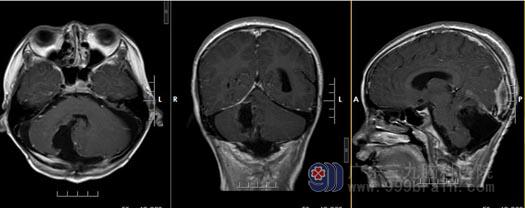

制定了详细的手术方案后,由鲁明副院长主刀将小锐的肿瘤在显微镜下全切除,术后复查MRI显示:原小脑半球巨大囊实性肿瘤已全切除,脑积水亦明显缓解。

▲术后MRI:原病变已全切除